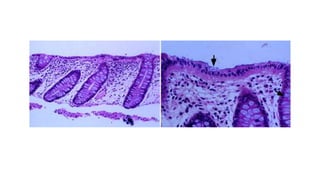

RELEVANT ANATOMY(2)

RELEVANT ANATOMY

(3)

• The superior rectal arteries and its branches

• The super and inferior hemorrhoidal

plexuses

• Hemorrhoids components- (a)mucosa

(b)stroma- blood vessels, smooth muscles

(c)anchoring connective tissue-secures the

hemorrhoids to the internal sphincter and

conjoined longitudinal coat.